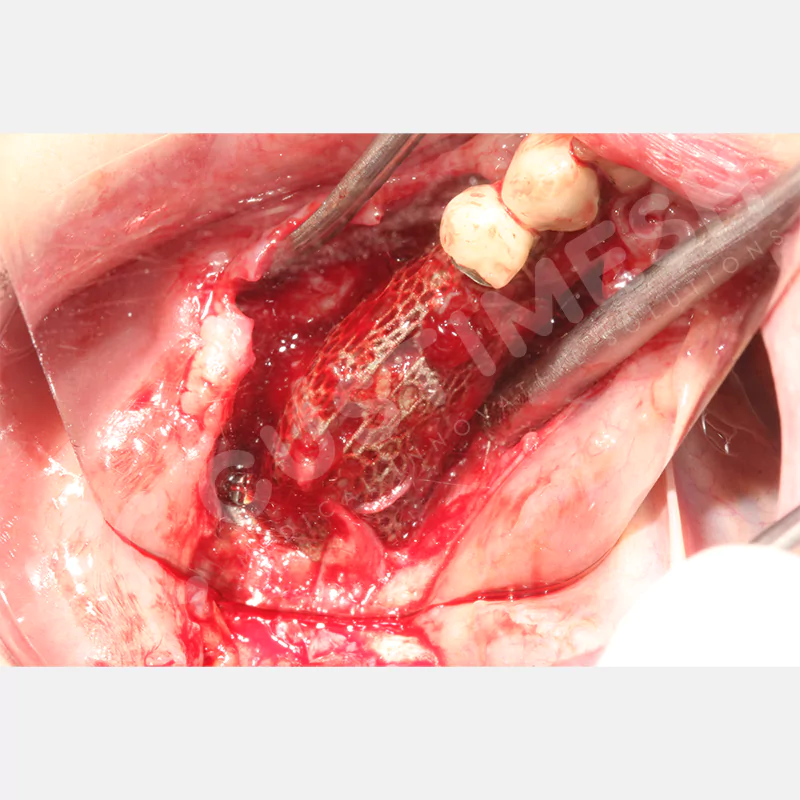

VAKA 3